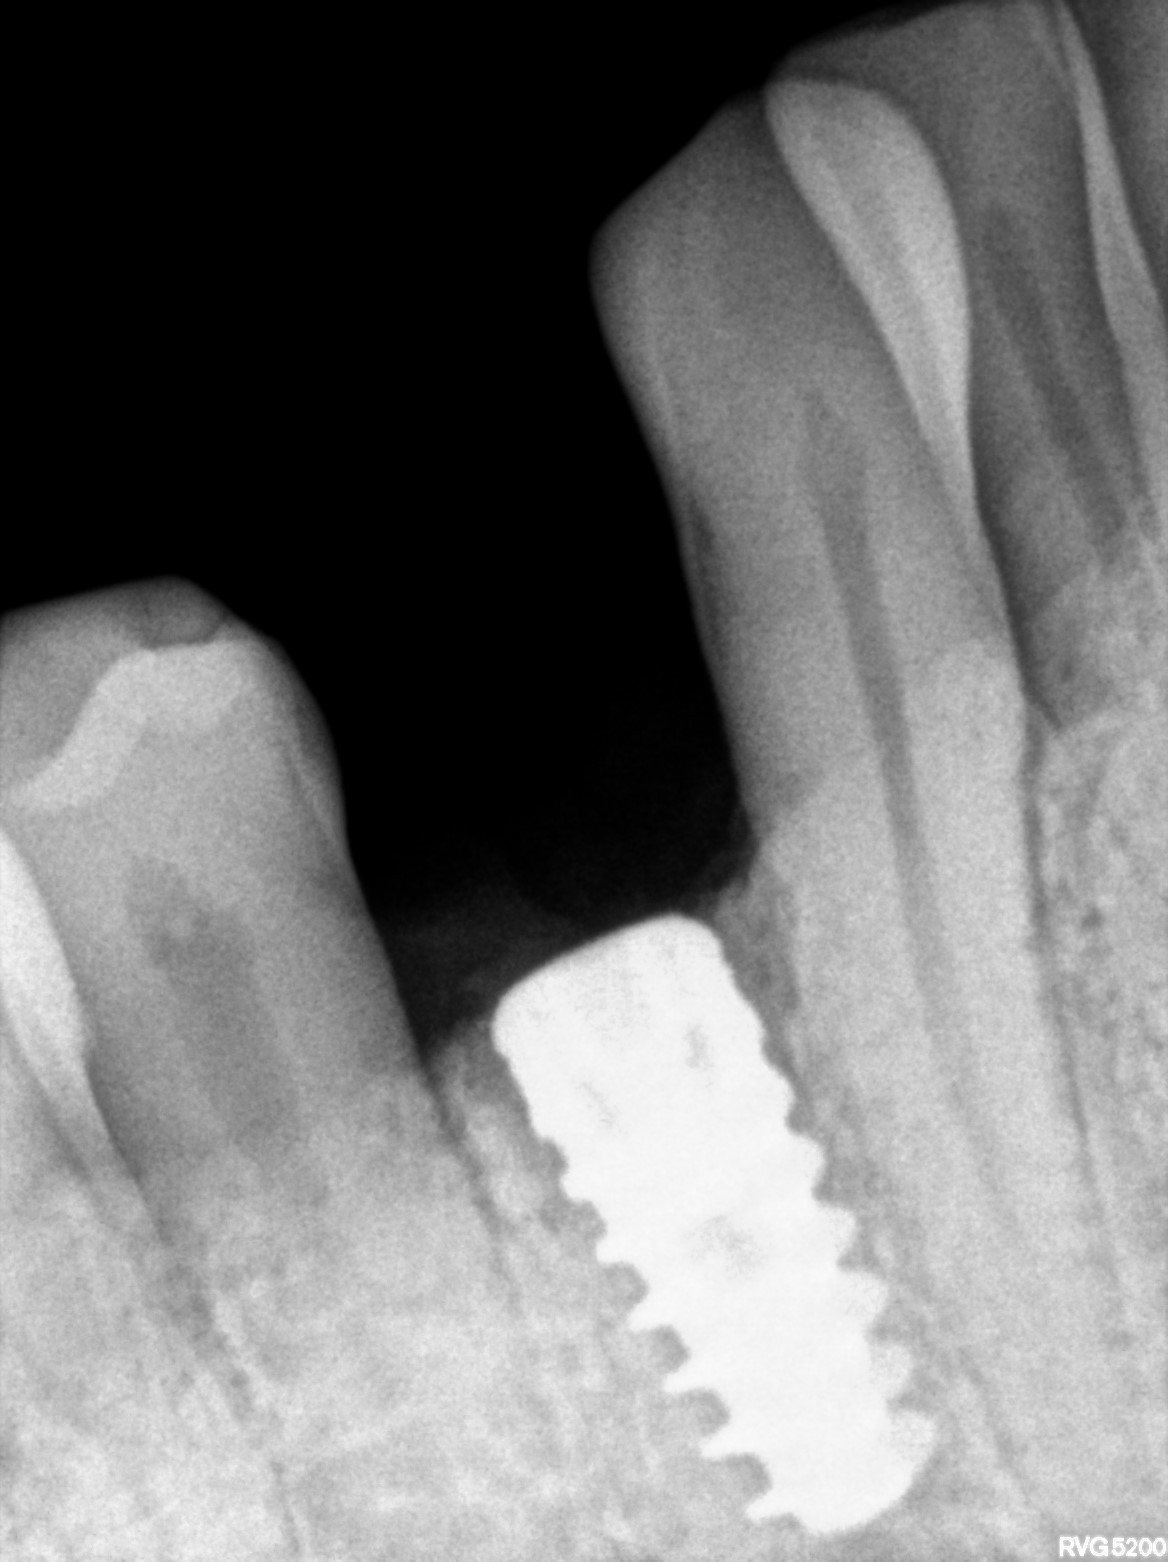

Dental Radiographs FHIR: DocumentReference · LOINC 24641-7

xray_1768234247_0.jpg

| Dental implant placement | 234781005 | D6010 Surgical placement of implant body | ##44 | 2026-01-12 | completed | implant placed w.r.t 44, adin implant 4.2*10 T-40N |

| Dental implant placement | 234781005 | — | ##44 | 2026-03-09 | completed | healing abutment placed with 44 | |